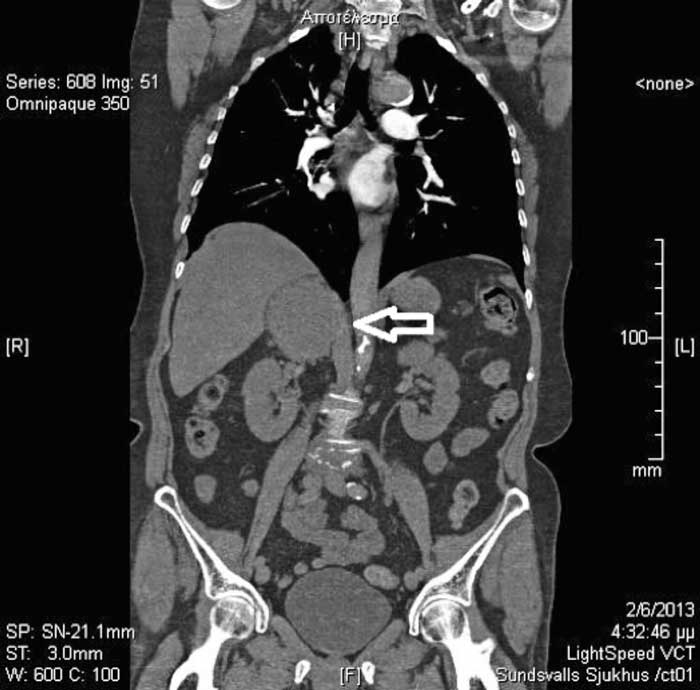

Fallbeskrivning